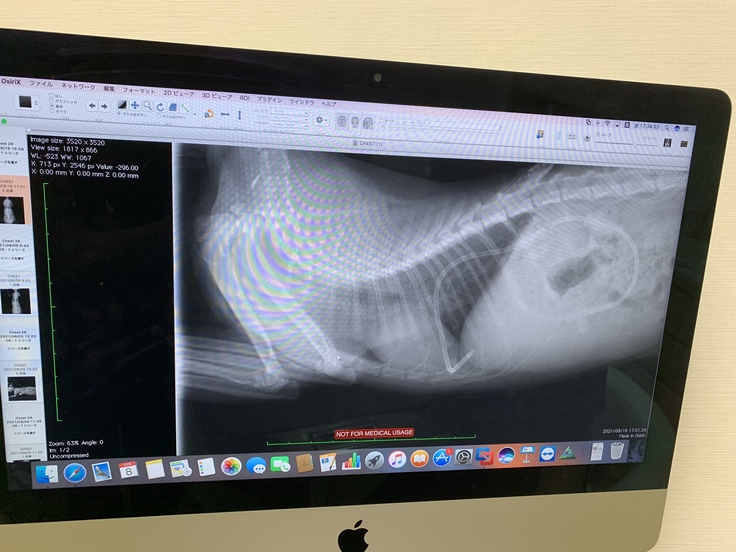

念の為レントゲンで胸水・腹水の有無確認

【10月14日】

ねこけんさん指導の元、血液検査とエコー検査をしてきました。

結果、膵臓辺りにドライタイプの症状である肉芽腫が発見されました。

このめはウエットタイプではなく、混合タイプでした。

(8月5日の時点でエコー検査は実施していましたが、異常はありませんでした)